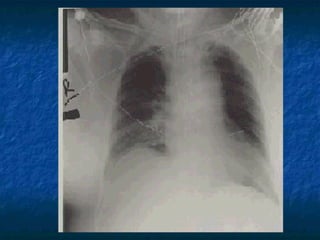

Chest X-Ray

Position of endotracheal tube

Position of central venous catheter

Pneumothorax, hemothorax, hydrothorax

Pulmonary edema, CHF

Cardiac silhoutte

Diaphragms

Rib fracture

Chest X-Ray Position ofendotracheal tube Position of central venous catheter Pneumothorax, hemothorax, hydrothorax Pulmonary edema, CHF Cardiac silhoutte Diaphragms Rib fracture